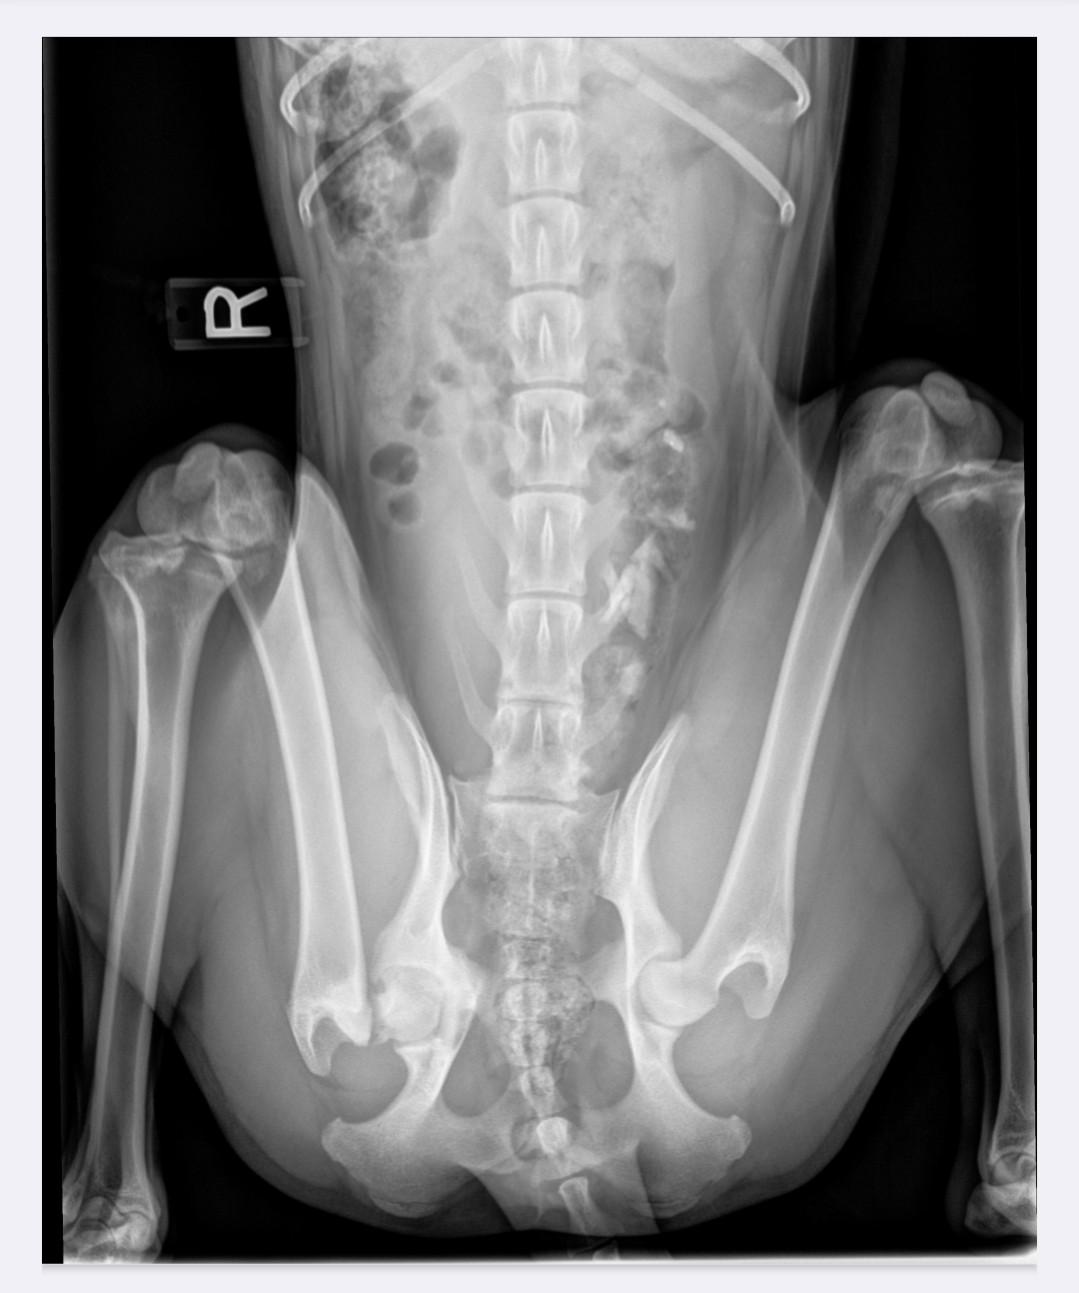

Robyn is a sweet, young border collie mix that came to a shelter as a stray with a limp. We were asked to help since the shelter was unable to pay for the potential treatment needed. We stepped in and got Robyn seen by an orthopedic vet who took x-rays and found an old broken right hip injury. Robyn’s body had scarred over the break, providing enough stabilization that she could walk and run with barely any noticeable limp. While in foster care, she mis-stepped getting out of the truck and fully broke off the ball of the femur (the part that goes into the hip socket). Robyn had emergency surgery to clean up the end of the broken bone, a procedure similar to an FHO (femoral head ostectomy). When she heals, Robyn’s body will scar around the hip to provide the stabilization needed for her to run and play again without pain. Will she be able a contender for the AKC agility championships? Probably not. But she can still be an active and playful dog who can live a full life.

For now, Robyn will need additional veterinary follow-up visits (paid for by WBCR) until she is fully cleared from the vet. There are also physical therapy exercises that her adopter will need to perform on her at home and adhere to exercise restrictions for at least the next couple months.